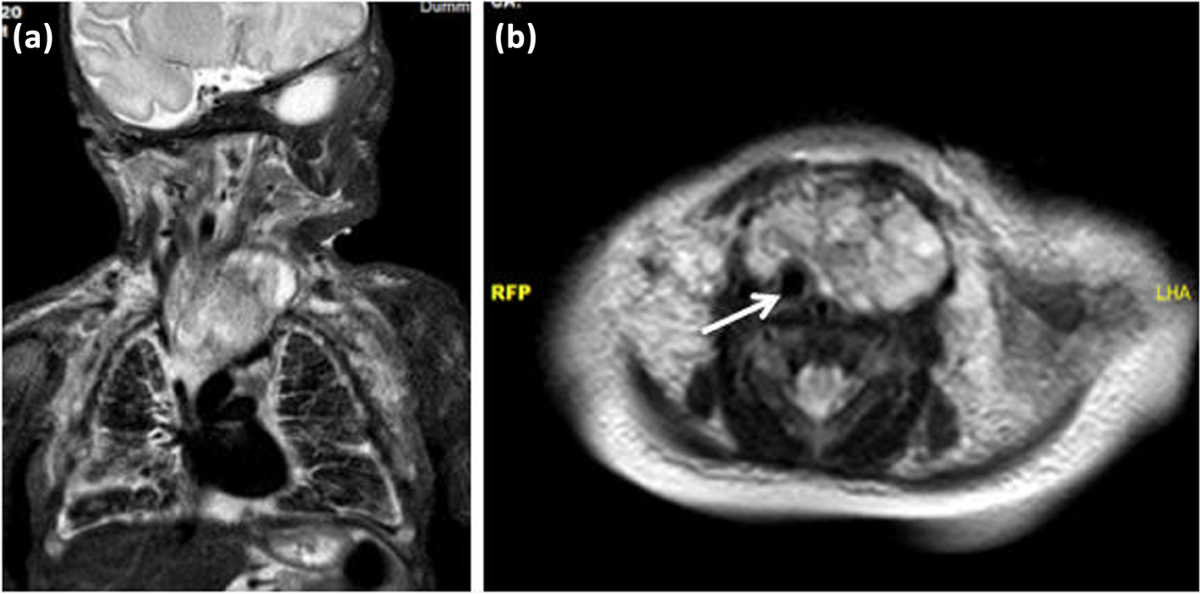

4-Mediastinal Kitleler (Teratom vb.)

Sorun

- Kalp ve büyük damar basısı

- Hidrops fetalis

Girişim

- Fetoskopik drenaj / damar koagülasyonu

- Nadiren açık fetal cerrahi